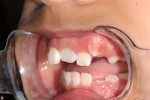

This is a 9yo girl with a high esthetic desire (wants to be a model/actor). She avulsed tooth #9 about 3 years ago, and she has been under treatment with other endodontists. I guess they attempted revascularization with MTA about year ago. #9 is ankylotic with a few mm’s infraposition. It is gray due to the MTA. #8 is slightly yellow/white due to calcification/obliteration but she says she feels cold testing and it is otherwise asymptomatic.

I spoke to her about the following options for #9:

1) Decoronation and a fake tooth for her teenage years

2) No treatment, except internal bleach then bonding/veneer.

3) Autotransplantation of a mandibular premolar

4) Segmental osteotomy/corticotomy later